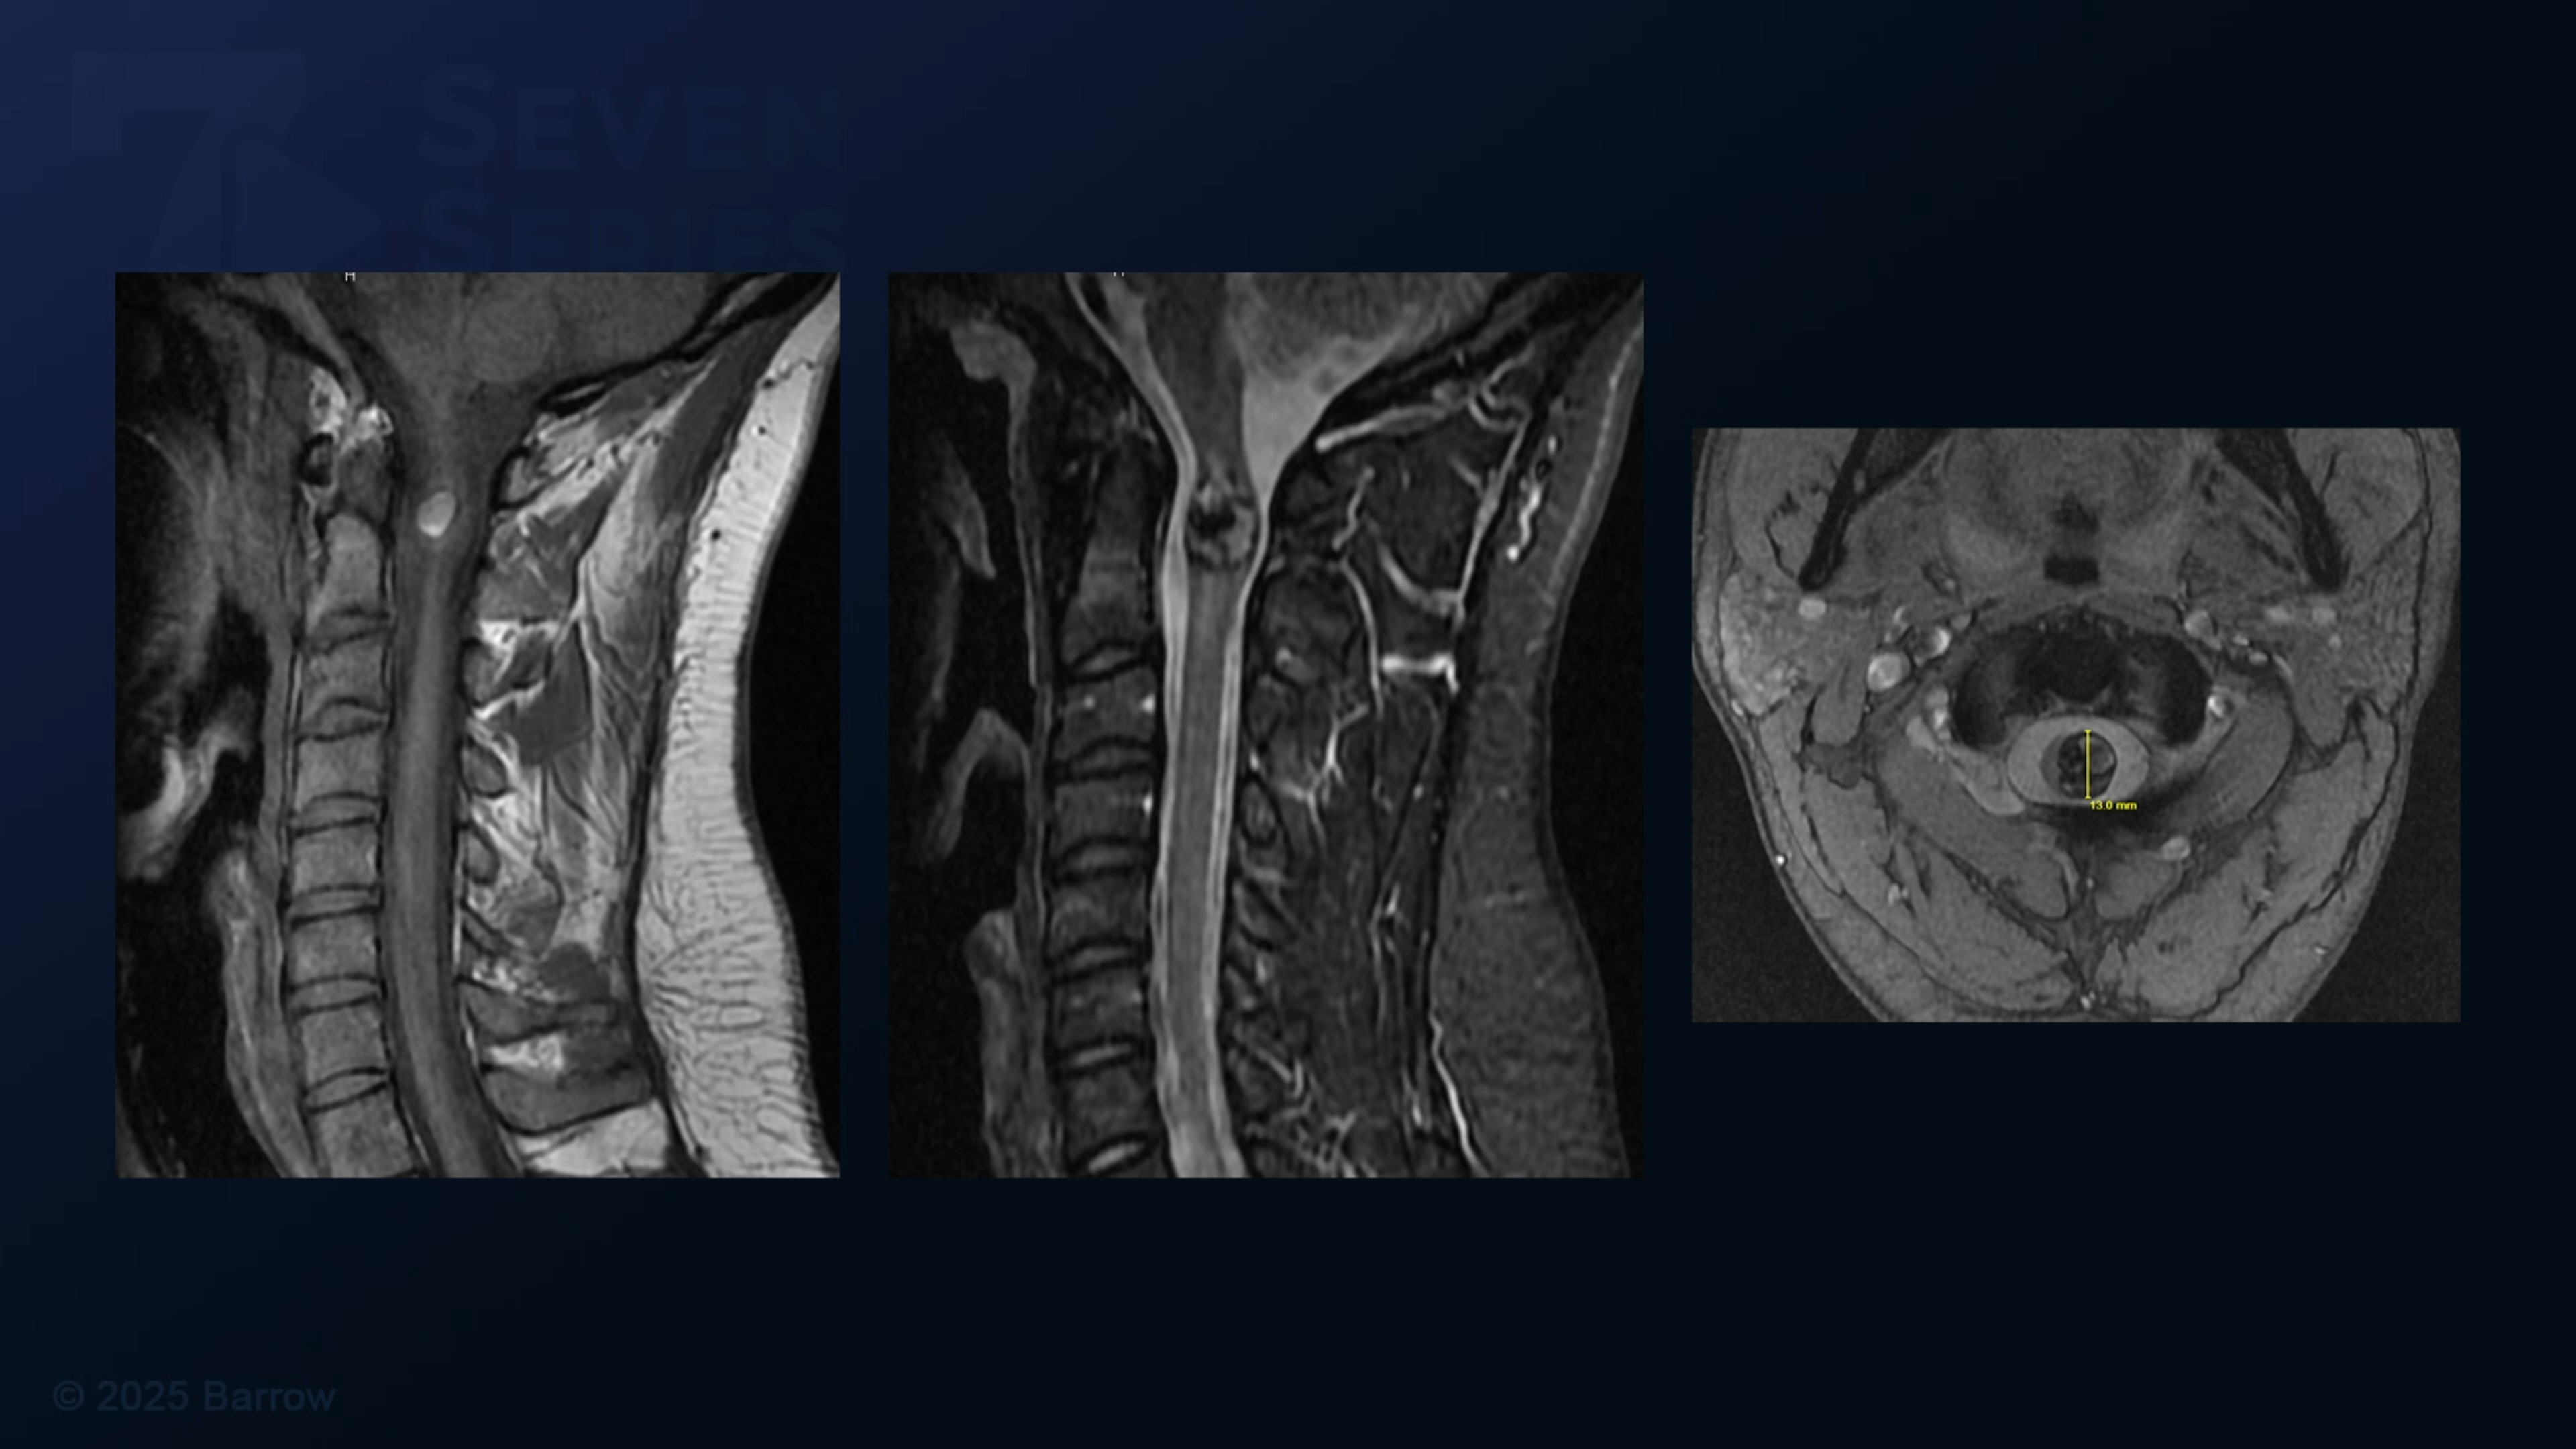

#487: Cervical C1-C3 Laminectomy for Spinal Cord Cavernous Malformation Resection

Episode 487 of Seven Series shows a cervical C1-C3 laminectomy for spinal cord cavernous malformation resection.